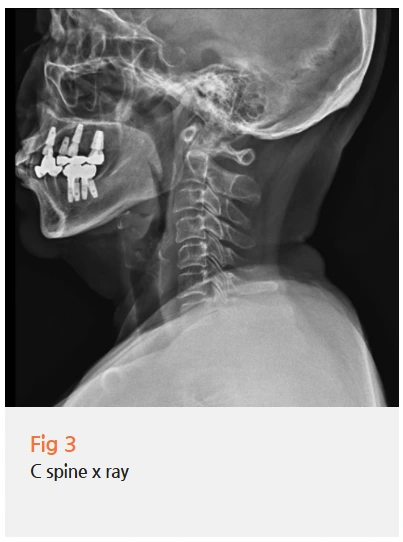

이 환자분께 저는 당일 뇌 MRI, MRA, 근전도 검사를 권유드렸어요.

삼차신경통 진단에서 영상 검사가 중요한 이유는

단순히 삼차신경통을 확인하는 것뿐 아니라, 이차적 원인을 배제하기 위함이에요.

✅ 혈관이 삼차신경을 압박하는 혈관성 병변이 있는지

✅ 뇌종양이나 수막종 등이 신경을 자극하고 있는 건 아닌지

✅ 다발성 경화증처럼 신경 자체의 탈수초 질환은 아닌지

이런 이차적 원인들이 있다면 접근 방법이 완전히 달라지기 때문에, 반드시 먼저 확인해야 합니다.

다행히 이 환자분의 뇌 MRI, MRA에서는 혈관 기형이나 종양, 염증 등의 소견은 없었어요.

이차적 원인 없이 삼차신경 자체의 이상으로 발생한 특발성 삼차신경통으로 진단되었습니다.